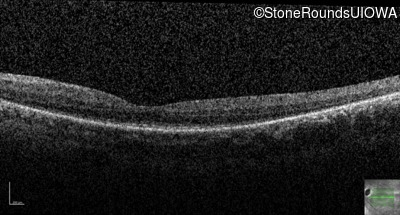

Optical Coherence Tomography - Left - 20/80 -2

Exemplar / OCT Stack